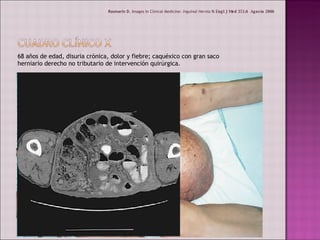

68 años de edad, disuria crónica, dolor y fiebre; caquéxico con gran saco herniario derecho no tributario de intervención quirúrgica. Rosmarin D , Images In Clinical Medicine:  Inguinal Hernia  N Engl J Med  355;6  Agosto 2006

68 años deedad, disuria crónica, dolor y fiebre; caquéxico con gran saco herniario derecho no tributario de intervención quirúrgica. Rosmarin D , Images In Clinical Medicine: Inguinal Hernia N Engl J Med 355;6 Agosto 2006